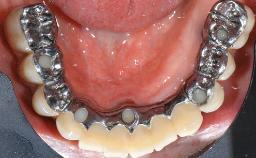

This case describes the ongoing management of a 64-year-old healthy, non-smoking female patient with erosive oral lichen planus (OLP) affecting the gingivae and the buccal and lingual mucosa. The peri-implant mucosa was also affected subsequent to implant placement. The patient had osseointegrated implants (four in the maxilla, four in the mandible) placed following extraction of hopeless teeth and a healing period. The patient had a history of OLP prior to implant placement and had been referred to an oral-medicine specialist for definitive diagnosis and treatment. She exhibited generalized oral mucosal involvement. Following a clinical assessment, biopsy, and blood tests, she was treated with topical corticosteroids. Systemic prednisolone was reserved for severe flare-ups. Amphotericin lozenges were used in combination with corticosteroid treatment to prevent the development of oral candidiasis.

| Prosthesis Type | FDP |

| Retention | Screw-retained, with 4 or more splinted implants Screw-retained, with 4 or more splinted implants |